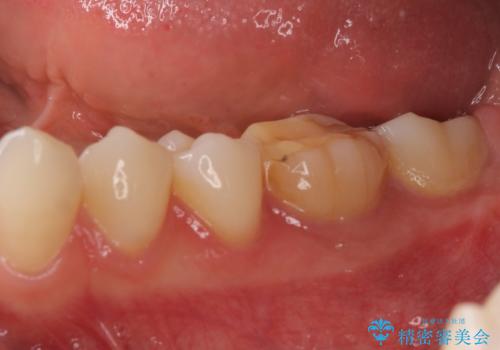

海外転勤が決まり、急いでセラミック治療をしてほしいとご来院された患者様です。

根管治療に症状がなく、上の歯に関しては土台もそのまま使用可能であったため、下の歯の土台、上下の歯のセラミック治療を行いました。

今回は幸い、症状がなく、根管治療の再治療が必要でないため、円滑に治療を進めることができました。